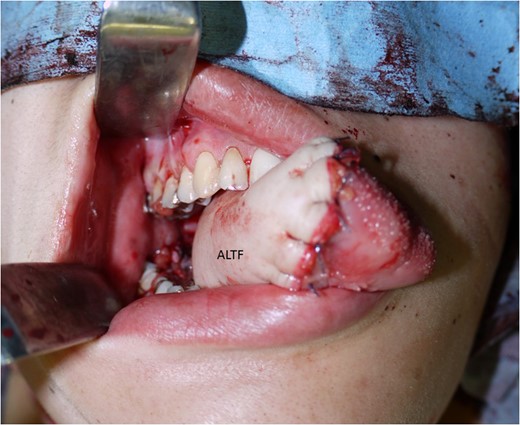

The surgical treatment for this patient involved tracheostomy, hemi-glossectomy and right-sided selective neck dissection when the patient was in her 28th week of pregnancy. Throughout the surgery, the patient was given a continuous intravenous infusion of ritodrine hydrochloride (100 mg in 500 ml) in order to provide tocolysis and prevent premature labour. A tracheotomy was preformed and the patient underwent a modified rapid sequence induction using fentanyl, thiopentone and rocuronium bromide. Anaesthesia was maintained with sevoflurane. A continuous fentanyl infusion provided analgesia and paralysis was maintained with boluses of atracurium besylate. Obstetricians were standing by for unexpected delivery. A cardiotocograph was used to monitor the foetus. The tissue defect was reconstructed with an antero-lateral thigh flap (Figs 3–5). The descending branch of lateral circumflex femoral artery was anastomosed to her right facial artery. One comitant vein was anastomosed to her external jugular vein in end-to-end fashion with a 2.5 mm microvascular anastomotic device. The other comitant vein was anastomosed in the same way to a branch of internal jugular vein with a 2.0 mm coupler. Heparin-saline solution (5000 units in 100 ml) was used to irrigate the anastomotic sites. Systemic heparin administration was not done during the operation. Lidocaine (2%) was used as vasodilator. Prostaglandin E1 was not administered. The operation took 7 h and 40 min. Blood loss was estimated to be 340 ml and no blood transfusion was required. Throughout the operation, no remarkable incidents were noted on the electronic foetal monitoring.

The antero-lateral thigh flap (ALTF) was pulled through, trimmed and sutured to fill the tongue defect.